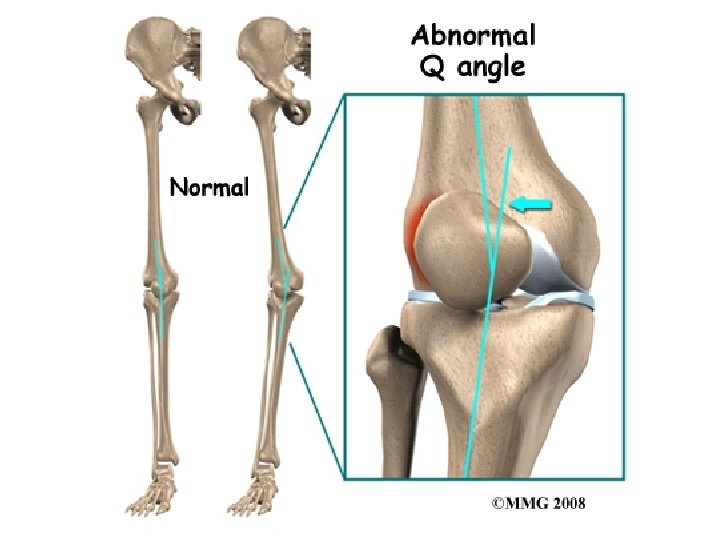

Quadriceps Angle “Q Angle” n n Adults typically 15 degrees Increases or decreases in the q angles are associated in cadaver models with increased peak patellofemoral contact pressures (Huberti & Hayes, 1984).

Increased Q Angle n n Femoral anteversion External tibial torsion Laterally displaced tibial tubercle Genu valgus

Quadriceps Angle “Q Angle” n Insall, Falvo, & Wise (1976) implicated increased q angle, along with patella alta, in a prospective study of patellofemoral pain.